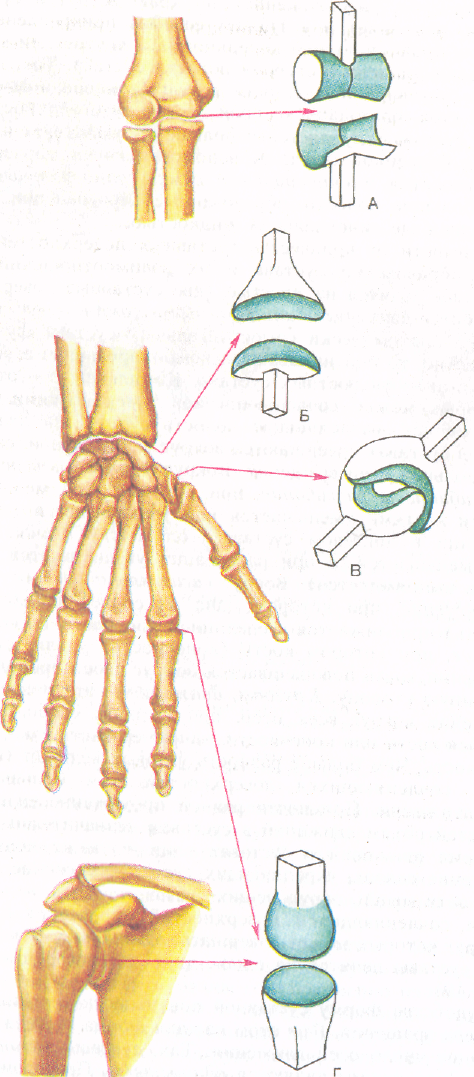

Диаграммы и схемы движения в суставах человека